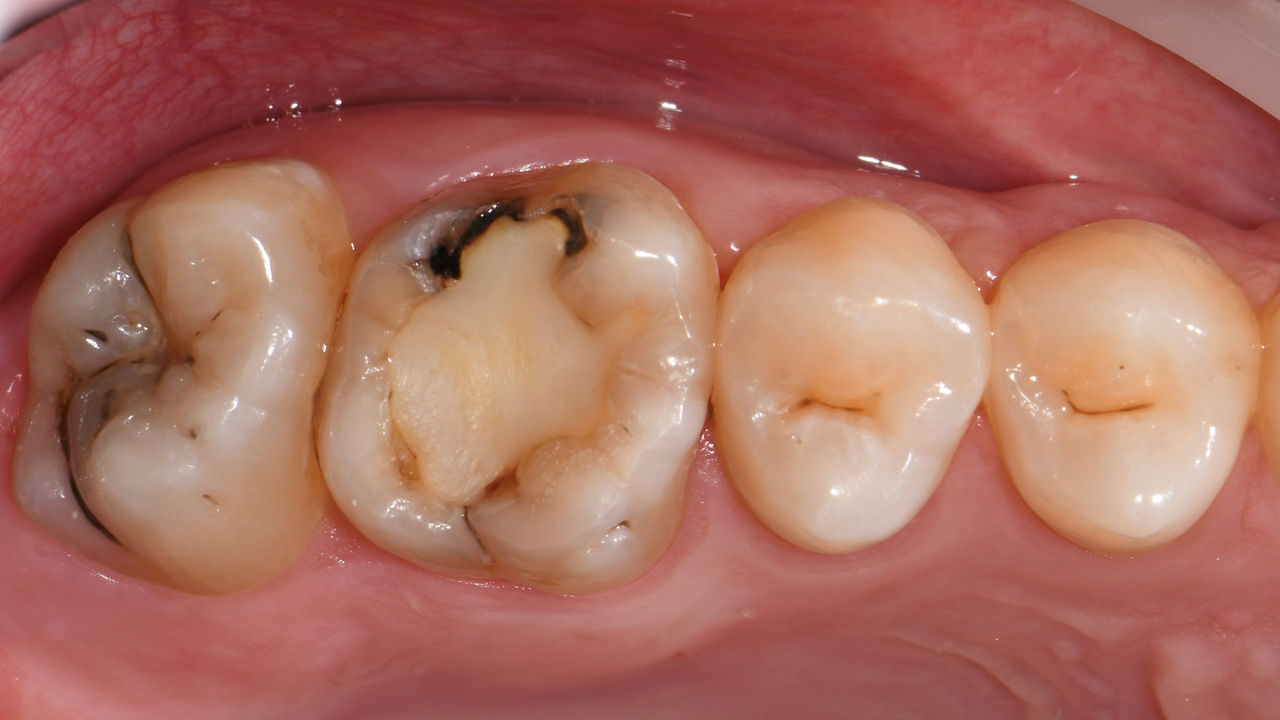

Before: Failed amalgam restoration needing replacement. Patient complaining of sensitivity and tooth presenting multiple cracks.

After: Chairside CAD/CAM partial crown restoration fabricated with CEREC Tessera Advanced Lithium-Disilicate glass ceramic.